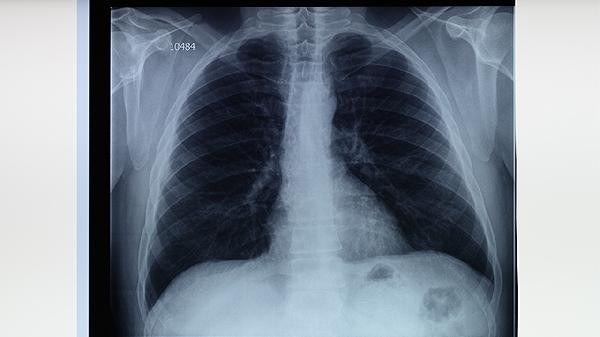

肺結(jié)核病灶會(huì)破壞肺泡和支氣管結(jié)構(gòu),形成空洞或纖維化病變,導(dǎo)致持續(xù)性咳嗽、胸痛和活動(dòng)后氣促。嚴(yán)重時(shí)可出現(xiàn)肺不張或毀損肺,長(zhǎng)期反復(fù)感染可能誘發(fā)慢性阻塞性肺疾病。治療需規(guī)范使用異煙肼片、利福平膠囊、吡嗪酰胺片等抗結(jié)核藥物,療程通常需6個(gè)月以上。

肺結(jié)核患者應(yīng)保證每日優(yōu)質(zhì)蛋白攝入量達(dá)1.2-1.5克/公斤體重,優(yōu)先選擇瘦肉、豆制品和乳清蛋白粉。康復(fù)期可進(jìn)行八段錦、呼吸操等低強(qiáng)度運(yùn)動(dòng),避免劇烈活動(dòng)加重缺氧。居住環(huán)境保持50%-60%濕度有利于呼吸道防護(hù),每3個(gè)月需復(fù)查胸部CT直至病灶穩(wěn)定。密切接觸者應(yīng)做結(jié)核菌素試驗(yàn)篩查,新生兒須接種卡介苗預(yù)防重癥結(jié)核。